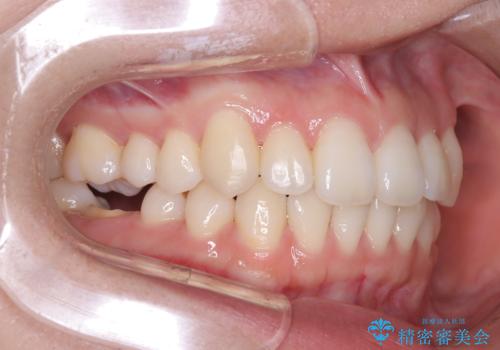

非抜歯矯正で八重歯を改善|短期間8か月で美しい歯並びに|インビザラインライト上顎のみで矯正

- 「八重歯を治したい」との主訴でご来院された患者様です。。

非抜歯で上顎のみインビザラインライトを使用して矯正を行いました。

短期間(約8か月)の治療で歯並びが整い、患者様も大変喜ばれました。